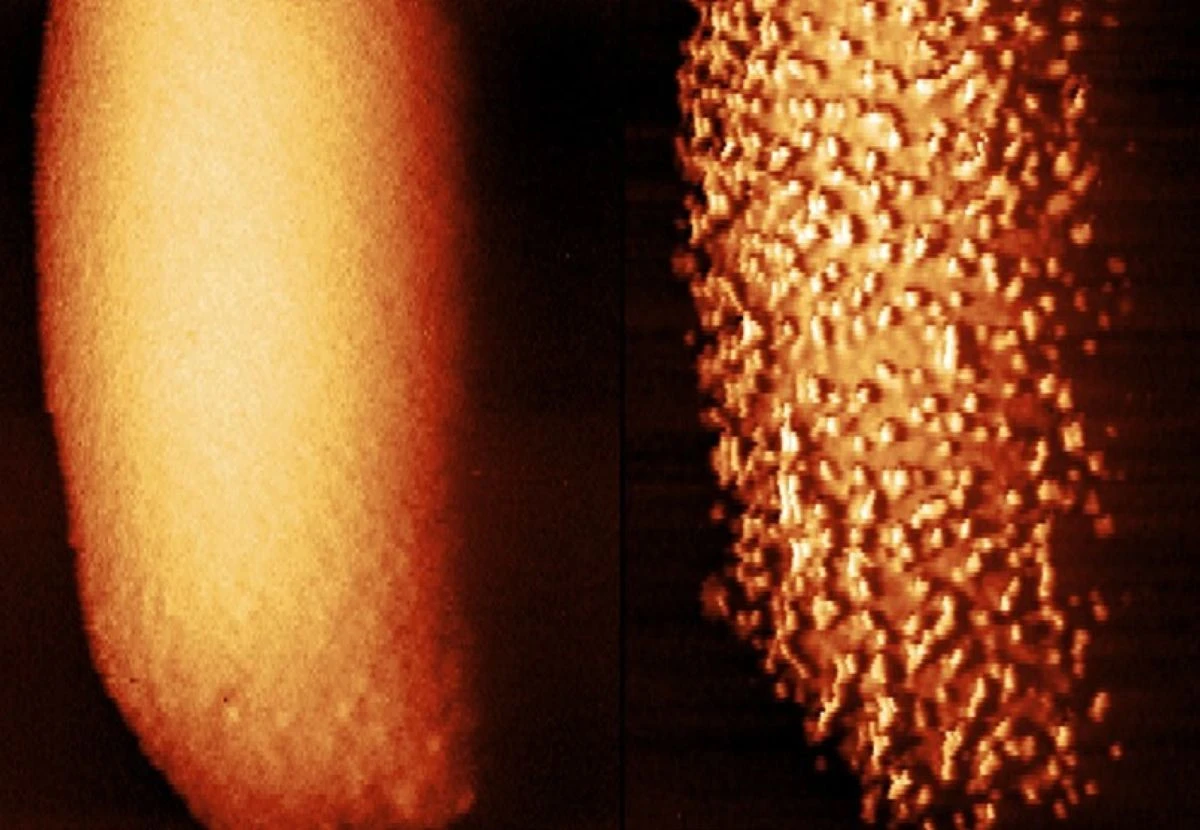

Η μελέτη πραγματοποιήθηκε από ερευνητές του University College London (UCL). Οι επιστήμονες χρησιμοποίησαν μια εξαιρετικά ακριβή τεχνική, γνωστή ως atomic force microscopy, η οποία επιτρέπει τη σάρωση επιφανειών με μια μικροσκοπική βελόνα ώστε να καταγραφούν αλλαγές στη δομή των κυττάρων σε επίπεδο νανομέτρου.

Χρησιμοποιώντας αυτή την τεχνολογία, κατάφεραν να καταγράψουν βήμα προς βήμα πώς το αντιβιοτικό επιδρά στα βακτήρια. Όπως εξηγεί η Carolina Borrelli, υποψήφια διδάκτορας βιοφυσικής και μικροβιολογίας στο UCL και συν-συγγραφέας της έρευνας, «ήταν απίστευτο να βλέπουμε σε πραγματικό χρόνο το πώς το αντιβιοτικό επιτίθεται στην επιφάνεια του βακτηρίου».

Οι εικόνες δείχνουν ότι όταν οι πολυμυξίνες έρχονται σε επαφή με το E. coli, αναγκάζουν την εξωτερική του μεμβράνη να σχηματίζει μικρούς όγκους και εξογκώματα. Αυτές οι παραμορφώσεις αυξάνονται μέχρι που η εξωτερική μεμβράνη –η «πανοπλία» του βακτηρίου– αποκολλάται και δημιουργούνται ρωγμές. Μέσα από αυτές τις ρωγμές, το αντιβιοτικό καταφέρνει να διεισδύσει στο κύτταρο και να το καταστρέψει.

Τα εν λόγω βακτήρια είναι γνωστά για τη διπλή τους μεμβράνη, η οποία περιβάλλει το κύτταρο σαν θωράκιση, καθιστώντας δύσκολη τη διείσδυση των περισσότερων φαρμάκων. Οι πολυμυξίνες στοχεύουν ακριβώς αυτή την εξωτερική μεμβράνη, προκαλώντας αστάθεια και τελικά πλήρη διάσπασή της.